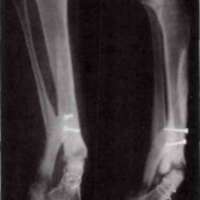

J.C. was born on October 27, 1948. He was injured by shrapnel on May 14, 1967, sustaining a fracture of the neck of the talus on the right leg and loss of soft tissue on the right heel. Fig. 8 shows the condition of his right ankle approximately five months after the injury.

|

The experimental brace was prescribed for this patient on November 21, 1967, and it was delivered on December 13. The prescription incorporated a SACH heel, a rocker bar, a reinforced foot plate, and no ankle motion. This patient experienced no particular problems other than the need for shoe changes. He found the brace useful and comfortable. X-rays taken on April 9, 1968, showed marked improvement (Fig. 9). His injuries proceeded to complete healing, and he is no longer wearing the VAPC brace.